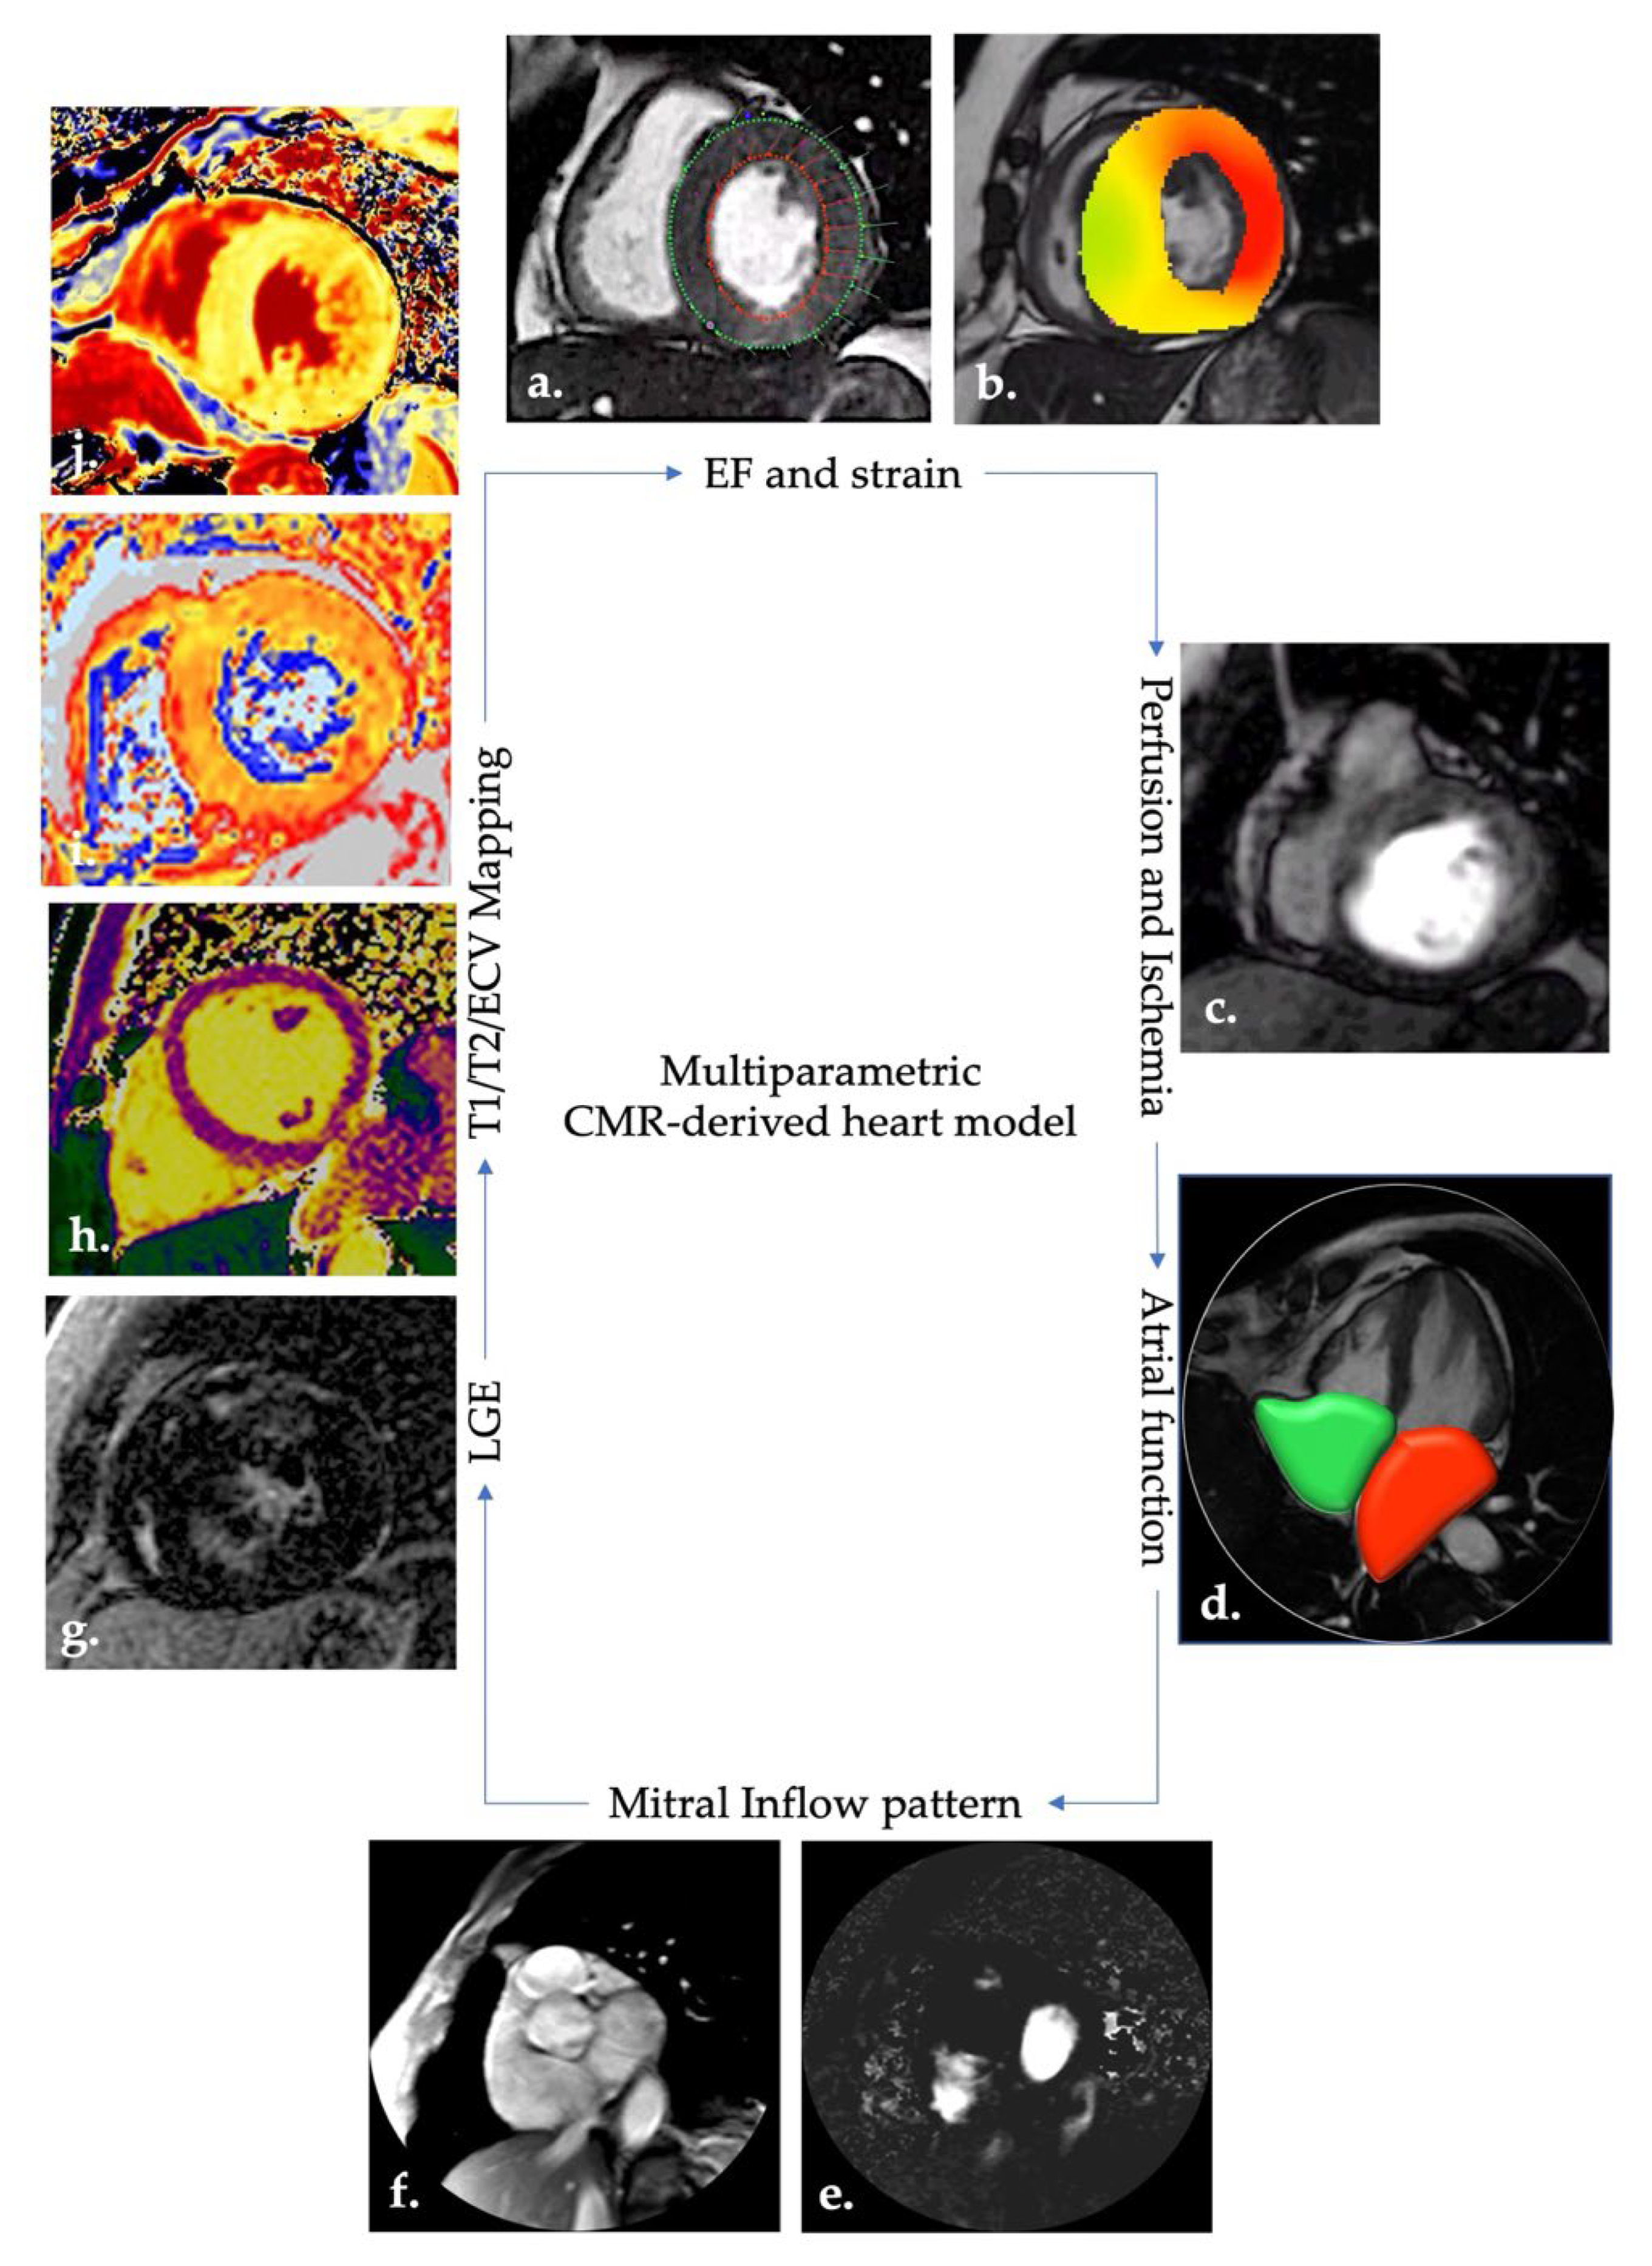

- CMR allows a holistic approach to cardiac patients.

2.1. HF Markers and CMR-CCTA Findings

2.1.1. Cardiac Function and Geometry

2.1.2. Subclinical Deformation Anomalies (Myocardial Strain)

2.1.3. Interstitial Matrix, LGE, T1, T2, and ECV Mapping

2.1.4. Transvalvular Inflow Pattern

2.1.5. Left Atrial Volumes and Function

2.1.6. Ischemia

2.1.7. Lung Involvement